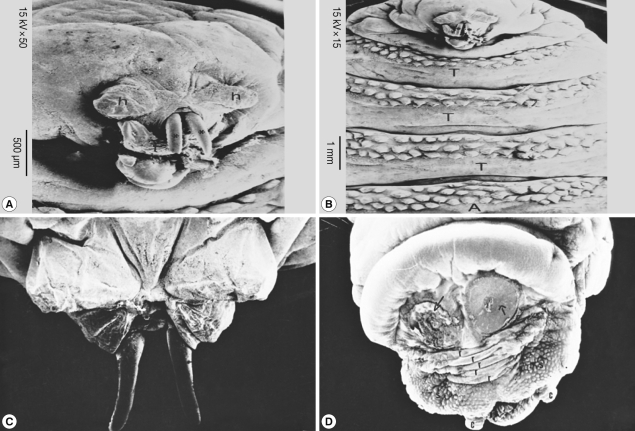

SEM findings

Scanning of the second stage larvae of Sarcophaga species showed that mouth hooks were smooth in outline. The mouth vestibule was pear-shaped. The sides of the cheek had lateral striations that were directed laterally and upwards (Fig. 4A, B). The anterior spiracles have 10 finger-like openings (Fig. 4C). The posterior spiracles were located in a deep cavity and each contains 2 elongated spiracular opening. At the posterior end, 6 pairs of papillae were observed, 2 pairs dorsal, 2 ventral, and 1 on each side of the posterior end (Fig. 4D).

Scanning of the third stage larvae of Sarcophaga species (Fig. 5) showed that the anterior end had a wide and strongly spined vestibular opening through which a longitudinally striped structure, ending in a curved sharp hook, protruded on each side (Fig. 5A). The dorsolateral aspect of each of these structures was provided with 2 anterior and 2 posterior processes (Fig. 5B). The anterior spiracles extended laterally from the second segment (Fig. 5C). Each of the 12 finger-like processes ended with more or less circular spiracle openings. The posterior end was surrounded by more pronounced spines (Fig. 5D). It was provided with 2 anal cerci and 8-10 pedunculated papillae. The posterior spiracles were not visualized since they were located in a very deep pit.

SEM of the third stage larvae of Oestrus species is shown in Fig. 6. The top view of the ventral surface of the larvae showed that the first segment (head) beared 2 ventrally curved hooks with pointed ends (Fig. 6A). The oral hooks extruded from the mouth orifice lying between a tongue-like process ventrally and 2 horn-like structures dorsally. The head was followed by 3 thoracic rings, with 3 regular rows of single-ended and caudally projected spines (Fig. 6B). The dorsal view of the anterior part of the larvae showed 2 protruded oral hooks and the extremity characterized by its butterfly shape (Fig. 6C). The posterior spiracles appeared strongly sclerotized surrounding the outlet of the respiratory canal completely, followed by 5 anal rides and 2 caudal swelling (Fig. 6D).

Fig. 4

SEM of the second stage larvae of Sarcophaga sp. Mouth hooks are smooth in outline. Lateral striations are on the side of the cheeks (A, B). The anterior spiracles have 10 finger-like openings (C). Posterior spiracles have 2 elongated spiracular opening (D).

Fig. 5

SEM of the third stage larvae of Sarcophaga sp. The anterior end has spined vestibular opening (A). The dorsolateral aspect is provided with 2 anterior and posterior processes (B). The posterior end of anterior spiracles (C) is surrounded with 2 anal cerci (D).

Fig. 6

SEM of the third stage larvae of Oestrus sp. The first segment (head) bears 2 ventrally curved hooks with pointed ends (A). Three thoracic rings, with 3 regular rows of single-ended caudally projected spines are seen (B). Two oral hooks (C) and 2 caudal swellings (D) are visible. T, thorax; A, abdomen.